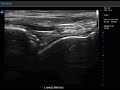

حقن البلازما الغنية بالصفائح الدموية في الكاحل